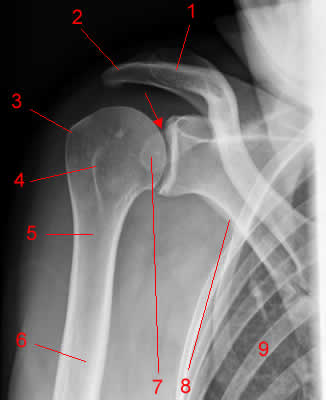

Radiografia do ombro

incidência AP (frontal).

1 Processo coracóide.2 Clavícula.3 Acrômio.4 Cabeça do úmero.5 úmero.6 Escápula (fronteira axilar)